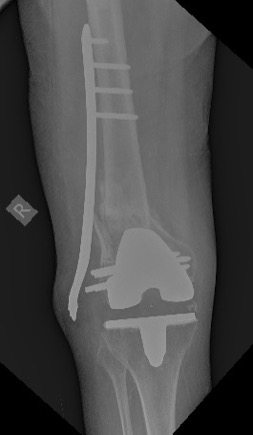

[Ortho] Перипротезный перелом дистального отдела бедра

Имя     : 0924.jpeg